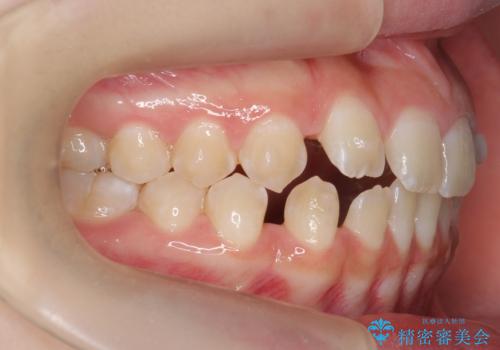

- 前歯の隙間を主訴に来院。

顎の大きさに比べて歯が小さく、隙間が目立っていました。

マウスピース矯正で隙間を閉じる処置を行いました。

隙間を閉じる際、奥歯が倒れたため、途中ワイヤー矯正を併用しています。